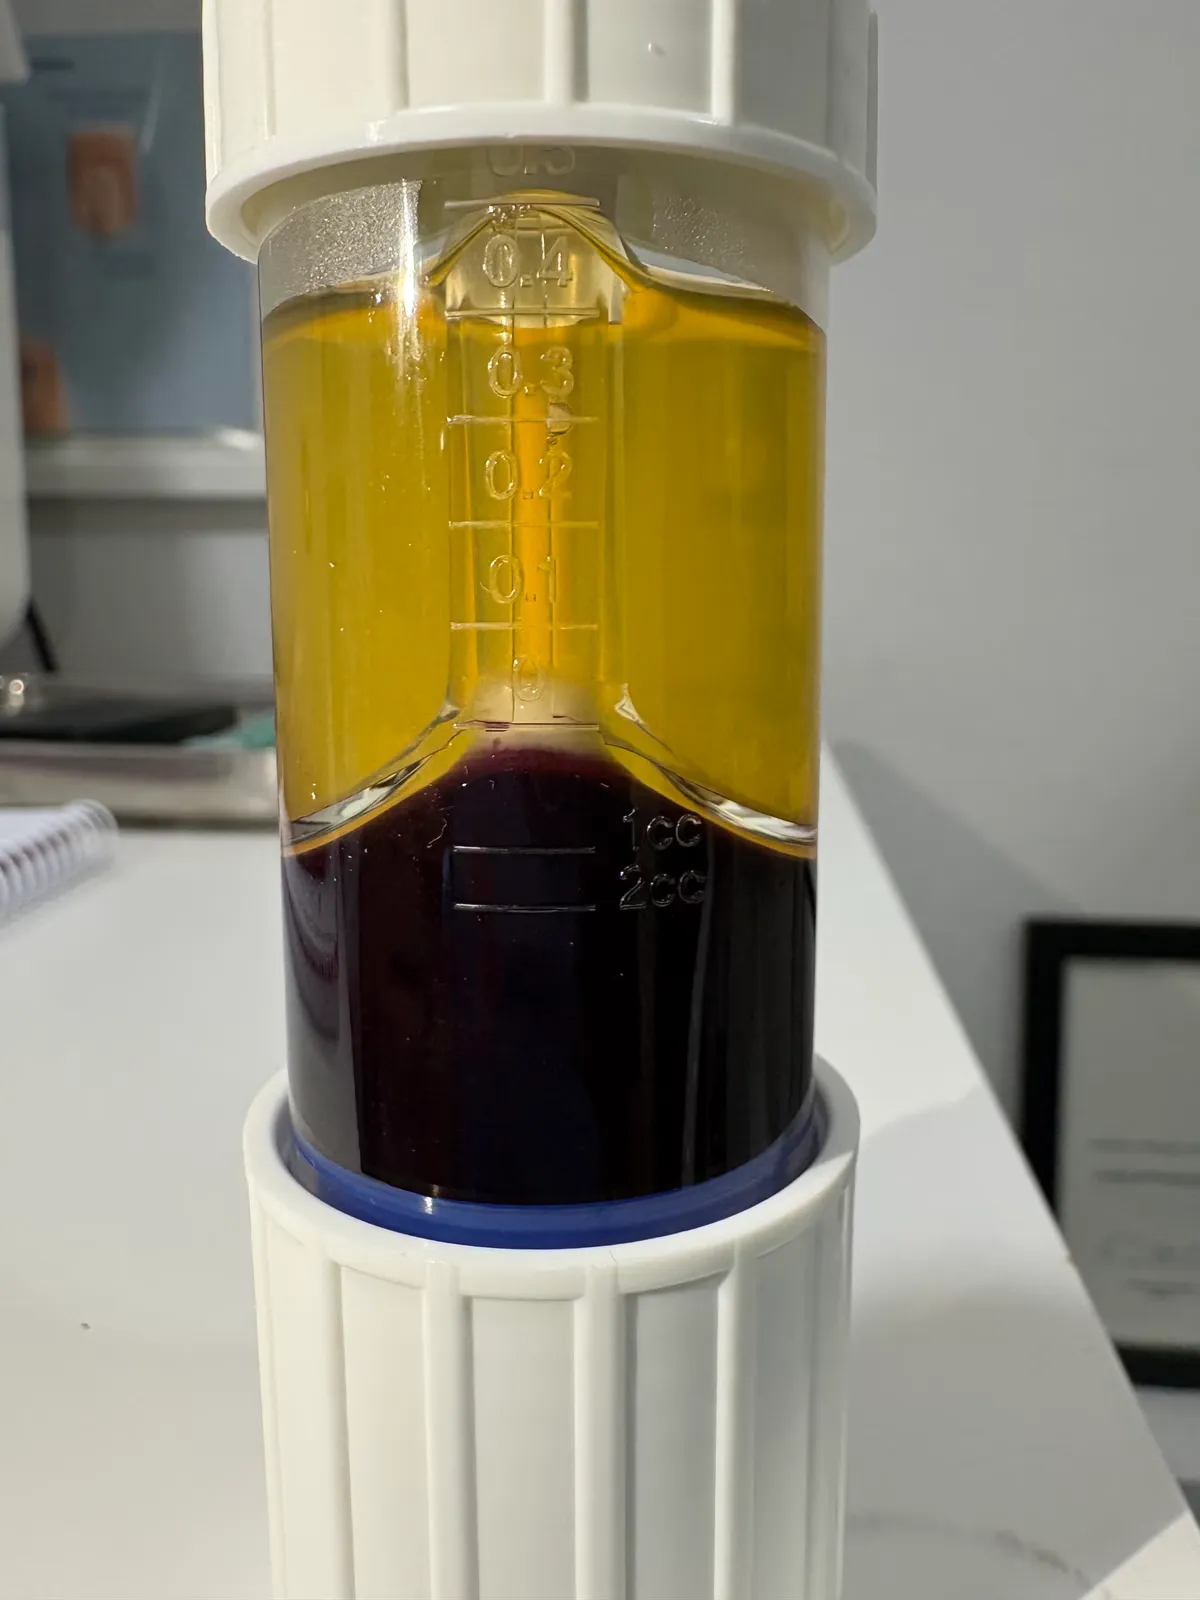

4. Ecografía Ungueal: Grosor del lecho ungueal, detección de masas/tumores, vascularización (Doppler), integridad de matriz.

Tecnología Diagnóstica Avanzada

- Ecografía de alta resolución (detecta masas <2mm)